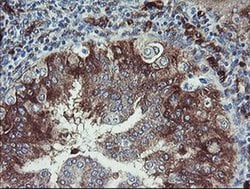

TSC22D1 Monoclonal Antibody (OTI1A5), Invitrogen™

TSC22 domain family protein, or TSC22, is a transcription factor that belongs to the large family of early response genes. This transcriptional repressor is known to act on the C-type natriuretic peptide (CNP) promoter. TSC22 belongs to the TSC-22/Dip/Bun family and is an intracellular protein that may be found in the cytoplasm or nucleus. This transcription factor is known to regulate cell growth, differentiation and cell death and is involved in modulating the transcriptional activity of Smad3 and Smad4. This protein is ubiquitously expressed in most tissues and widely in both fetal and adult tissues. It is generally expressed in aortic endothelial cells, and induced by cytokines, including TGFB. These proteins may be possible therapeutic targets of leukemia and prostate cancer.

| Immunohistochemistry (Paraffin), Western Blot | |